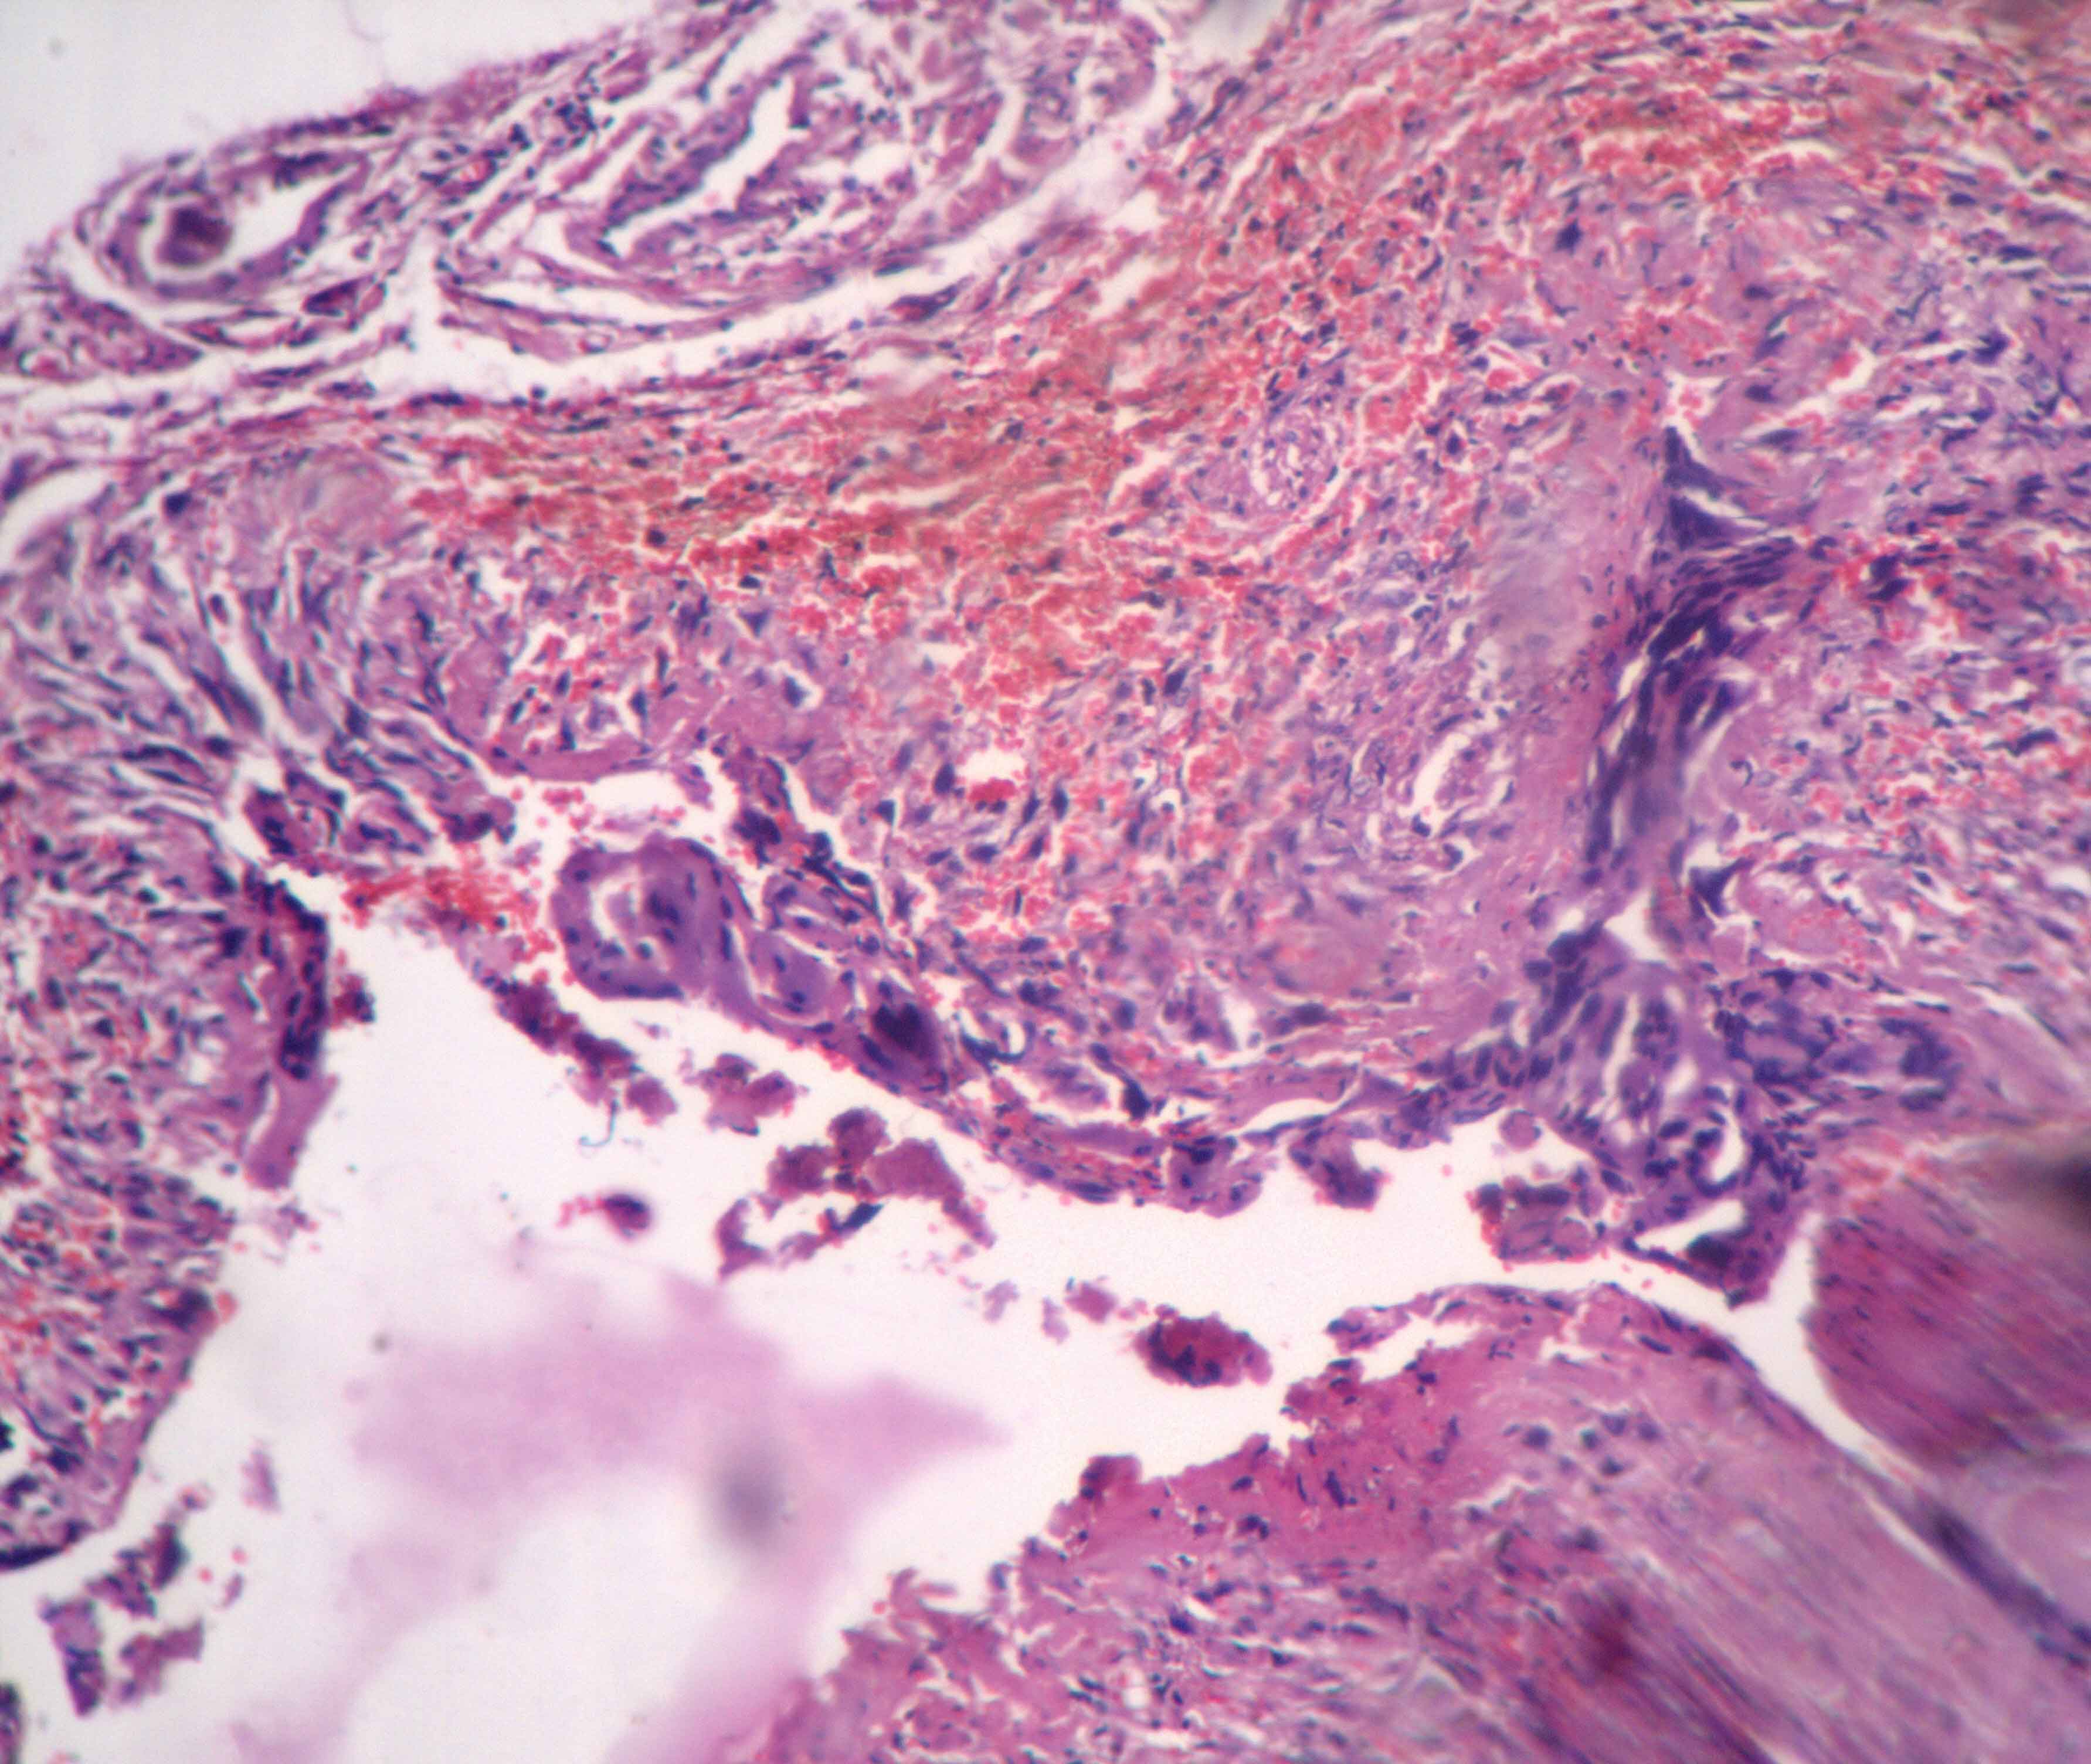

Histopathological findings: Left fallopian tube was 5cms in length and was within normal limits. Right fallopian tube was 7.5cms in length and dilated at distal end with a defect measuring 1x1 cms covered by grey-white exudate. Cut surface showed blood clot with grey brown material in the lumen and wall thickened. The bits were given from the ruptured area and proximal part of the tube. Microscopically distal segment of right fallopian tube showed decidual tissue bits mainly composed of cytotrophoblastic and synctiotiotrophoblstic cells with no chorionic villi [Table/Fig-1]. Proximal (isthmus) portion of tube revealed cystically dilated glands entrapped in hypertrophic muscular layer and the glands were lined by ciliated columnar epithelium [Table/Fig-2]. With these histopathological features, the final diagnosis of isthmic ectopic pregnancy and salpingitis isthmica nodosa was made.

Cystically dilated glands trapped in the muscular layer (H & E, x 40)